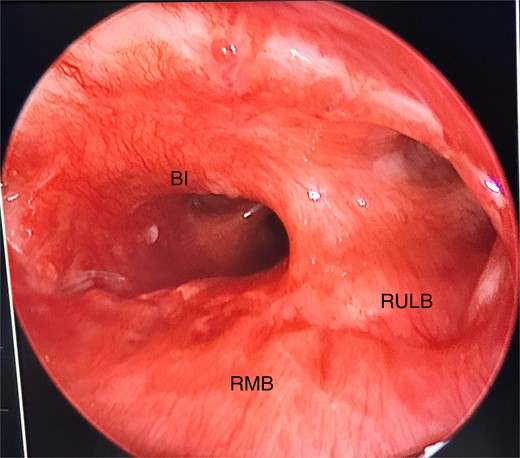

She initially underwent a rigid bronchoscopy, biopsy of the endobronchial tumour, cryoablation, and argon plasma for debulking. On direct visualization with the telescope the tumour was polypoid and was arising from the membranous portion of the right main bronchus (RMB) (Fig. 2).

Initial rigid bronchoscopy showing a polypoid mass originating from the membranous portion of the right main bronchus; BI, bronchus intermedius; RMB, right main bronchus.